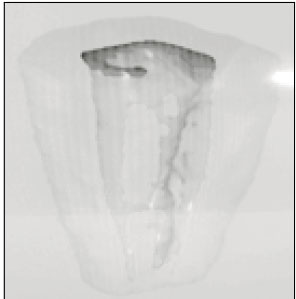

30 mandibular molars with C-shaped root were selected. Six photo images from occlusal, apical, mesial, distal, buccal, lingual directions and radiographic view were taken as preoperative ones to compare them with 3-D image. After crown reduction to the level of 1-2mm over pulpal floor was performed, teeth were stored in 5.25% sodium hypochlorite solution for the removal of pulp tissue and debris. They were cleaned under running water, allowed to bench dry and embedded in a self-curing resin. This resin block was serially ground with a microtome (Accutom-50, Struers, Denmark) and the image of each level was recorded by digital camera (FinePix S1-pro, Fuji Co., Japan). The thickness of each section was 0.25mm. Photographs of serial sections through all root canal were digitized using Adobe Photoshop 5.0 and then minimum thickness of open and closed sites were measured (open site is the surface containing occluso-apical groove : closed site is oppsite). After dizitization using 3-D Doctor (Able software Corp, USA), 3D reconstruction of the outer surface of tooth and the inner surface of pulp space was made. Canal classsification of C-shaped roots was performed from this 3-D reconstructed image.

Conclusively, 3D reconstruction method could make the exact configurations of C-shape root possible to be visualized and analyzed from multi-directions. Data from minimum thickness recommend cleaning and shaping be more carefully done on dangerous mid portion.